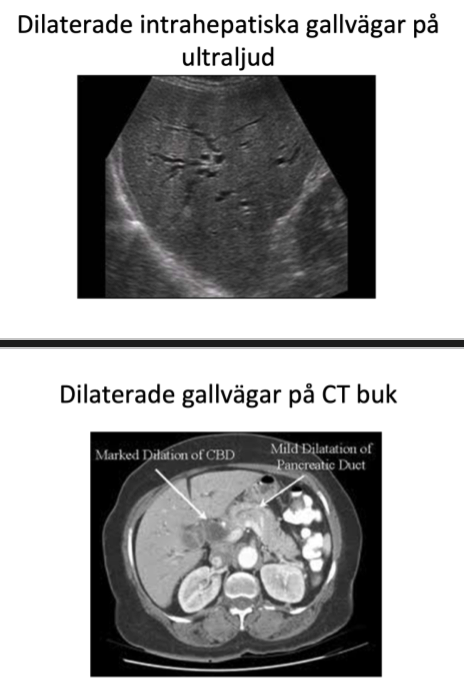

1. Nämn dem 3 vanligaste orsakerna till stasikterus

1. sten i papill ger ökad risk för samtidig pankreatit

2. Cholangit. Infektion i gallvägarna som leder till sepsis obehandlad.

3. Genomlysning med kontrast.

4. Papillotomi - vidgning av papilla vateri med endkskopet för att kunna komma in i gallgången.